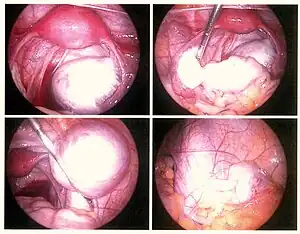

Laparoscopy

Laparoscopy, a surgical procedure where a camera is used to look inside the abdominal cavity, is the only way to accurately diagnose the extent and severity of pelvic/abdominal endometriosis.[94] Laparoscopy is not an applicable test for extrapelvic sites such as umbilicus, hernia sacs, abdominal wall, lung, or kidneys.[94]

Laparoscopy permits lesion visualization unless the lesion is visible externally (e.g., an endometriotic nodule in the vagina) or is extra-abdominal.[94] If the growths (lesions) are not visible, a biopsy must be taken to determine the diagnosis.[97] Surgery for diagnoses also allows for surgical treatment of endometriosis at the same time.

During a laparoscopic procedure lesions can appear dark blue, powder-burn black, red, white, yellow, brown or non-pigmented. Lesions vary in size.[98] Some within the pelvis walls may not be visible, as normal-appearing peritoneum of infertile women reveals endometriosis on biopsy in 6–13% of cases.[99] Early endometriosis typically occurs on the surfaces of organs in the pelvic and intra-abdominal areas.[98] Health care providers may call areas of endometriosis by different names, such as implants, lesions, or nodules. Larger lesions may be seen within the ovaries as endometriomas or "chocolate cysts", "chocolate" because they contain a thick brownish fluid, mostly old blood.[98]